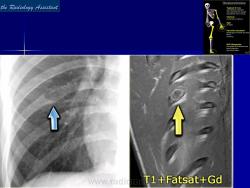

Энхондрома (син.: хондрома, центральная хондрома) — доброкачественная хрящевая опухоль, расположенная в костномозговом канале (интрамедуллярно). Встречается в 10 % случаев от общего числа доброкачественных опухолей костей. Считается, что она возникает из эктопически расположенных островков хряща, отщепившегося от пластинки роста на ранних этапах онтогенеза. В ряде случаев опухоль остается бессимптомной и обнаруживается случайно при рентгенологическом исследовании. В других случаях возникают боль и припухлость. Обычно болезненными становятся все энхондромы фаланг. Наиболее частая локализация: фаланги, главным образом, пальцев кистей, проксимальный конец плечевой кости, проксимальный или дистальный концы бедренной кости. При рентгенологическом исследовании в энхондроме определяются просветления с участками минерализации. Тень кости становится более широкой, кортикальный слой сохраняет целостность, но истончается. В редких случаях энхондрома имеет вид эксцентрически растущего экзофитного новообразования. Макроскопически опухоль представляет собой голубовато-белую полупрозрачную хрящевую ткань, в которую вкраплены желтоватые участки обызвествления. Опухоль состоит из отдельных хрящевых узелков, диаметр которых варьирует в пределах 1 см.

Энхондроматоз (син, болезнь Оллье) — редкая врожденная патология, не передающаяся по наследству, при которой у больных имеется множество доброкачественных хрящевых опухолей, главным образом на конечностях. Пораженная конечность укорачивается и деформируется. После завершения полового созревания заболевание не прогрессирует. Возможна малигнизация, которая отмечается в возрастном промежутке 13—69 лет. Локализация: энхондромы обнаруживаются в метафизах, диафизах, эпифизарных пластинках и суставных хрящах. Это интракортикальные и/или периостальные поражения в виде отдельных опухолей, не сливающихся друг с другом. Им присущ основной признак энхондроматоза — богатство клетками (гипериеллюлярность), причем встречается много двуядерных хондроцитов. И гиперцеллюлярность, и цитологическая атипия при энхондроматозе выражены значительнее, чем при солитарной энхондроме.

Рентгенологическая картина хондромы представляет четко очерченный опухолевый узел. Очаги минерализации в хондромах выглядят достаточно характерно и представлены очаговыми, глыбчатыми или кольцевидными , арочными отложениями извести. Полного разрушения кортикального слоя трубчатой кости с выходом опухолевых масс в мягкие ткани не наблюдается.